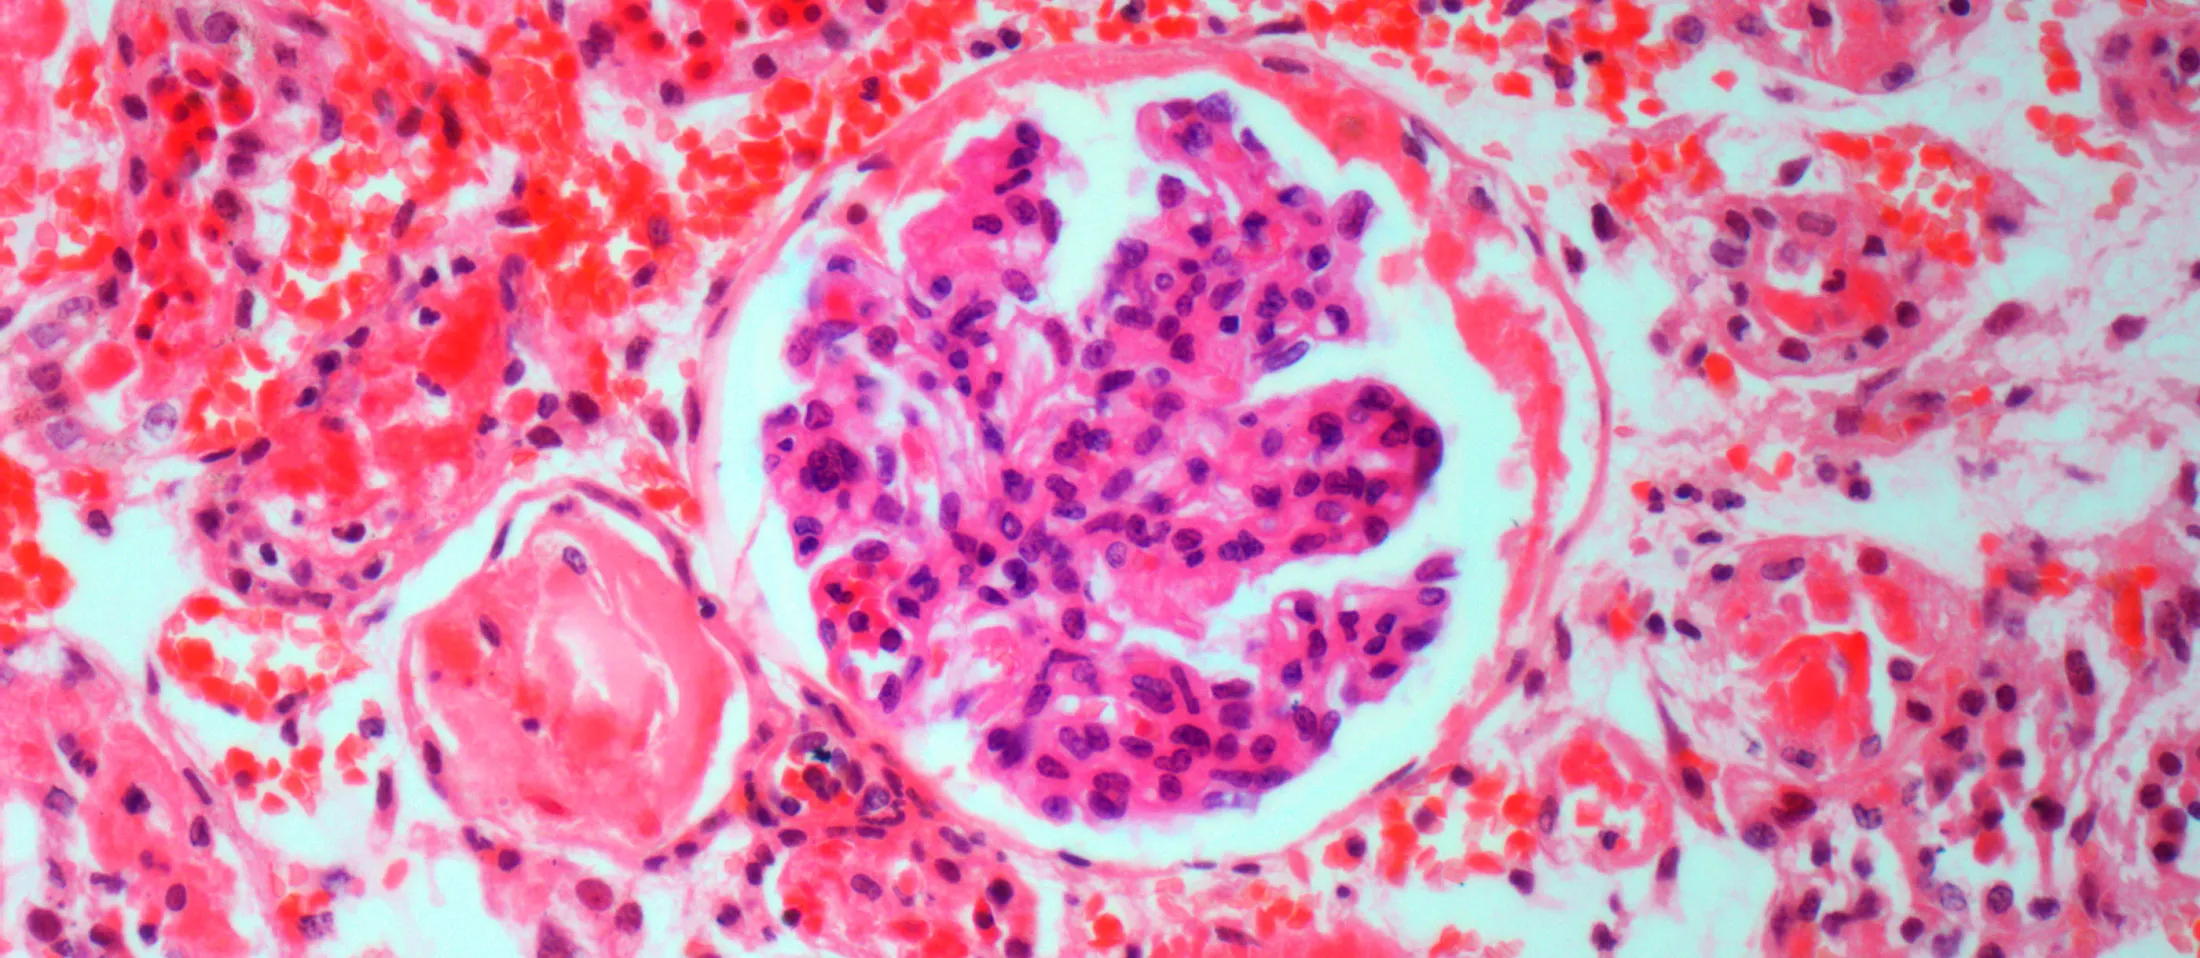

Light micrograph of kidney disease.